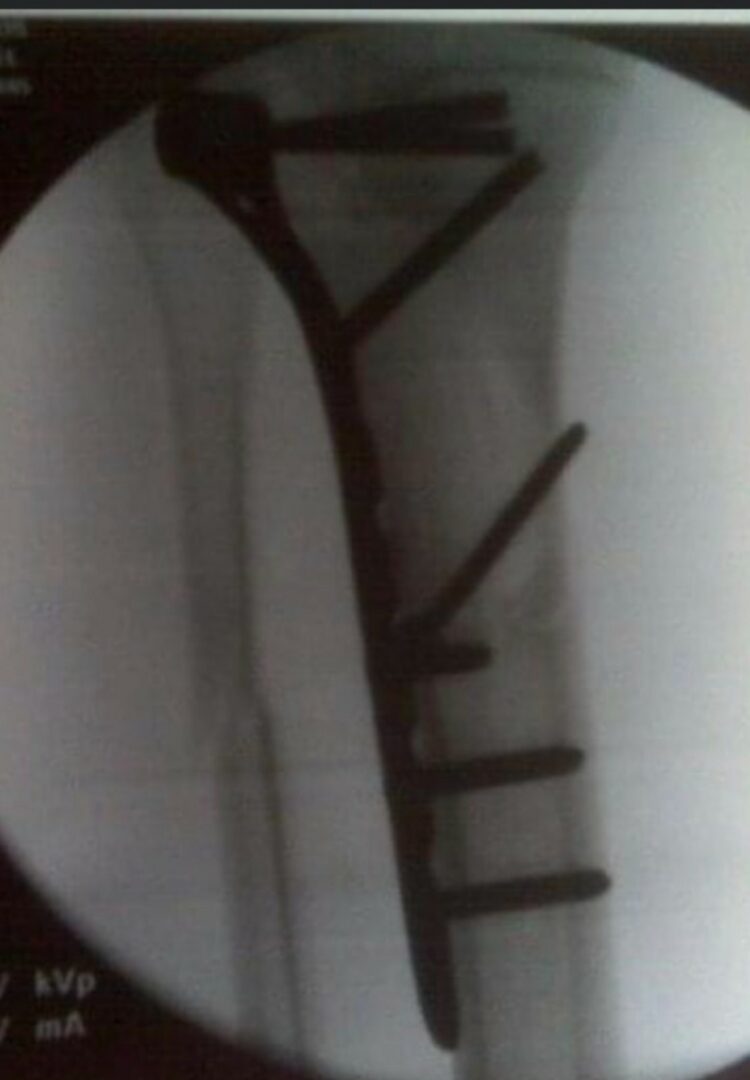

I’ve been through so much in life at a young age with family, at a teenage age battling back from knee, shin, and heart surgeries. But I’ve always come out on top from the lessons life gave me as a young kiddo. World may be in chaos around you, but you still have to pick up that hammer and get back to work.